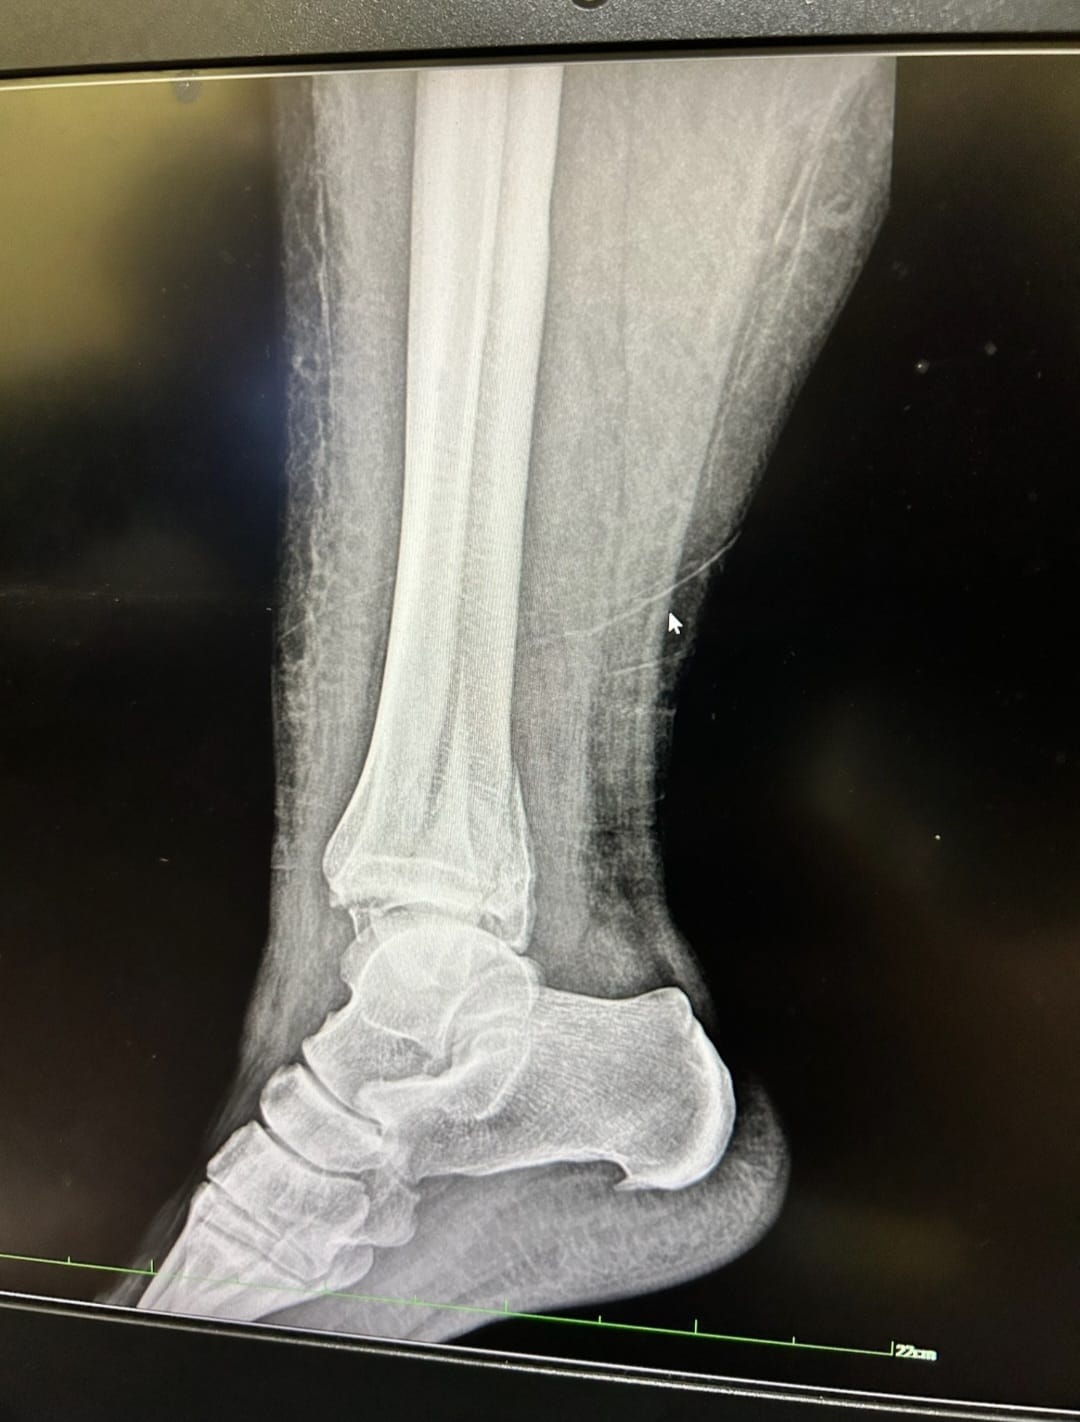

While serving on a medical mission in Guatemala in March 2024, Nikki sustained a serious ankle fracture—an injury that left her suddenly immobile, uncertain, and afraid. As an ICU nurse at Regions Hospital in the Twin Cities of Minnesota, she understood the medical realities of trauma, but that knowledge didn’t remove the emotional weight of becoming a patient herself.